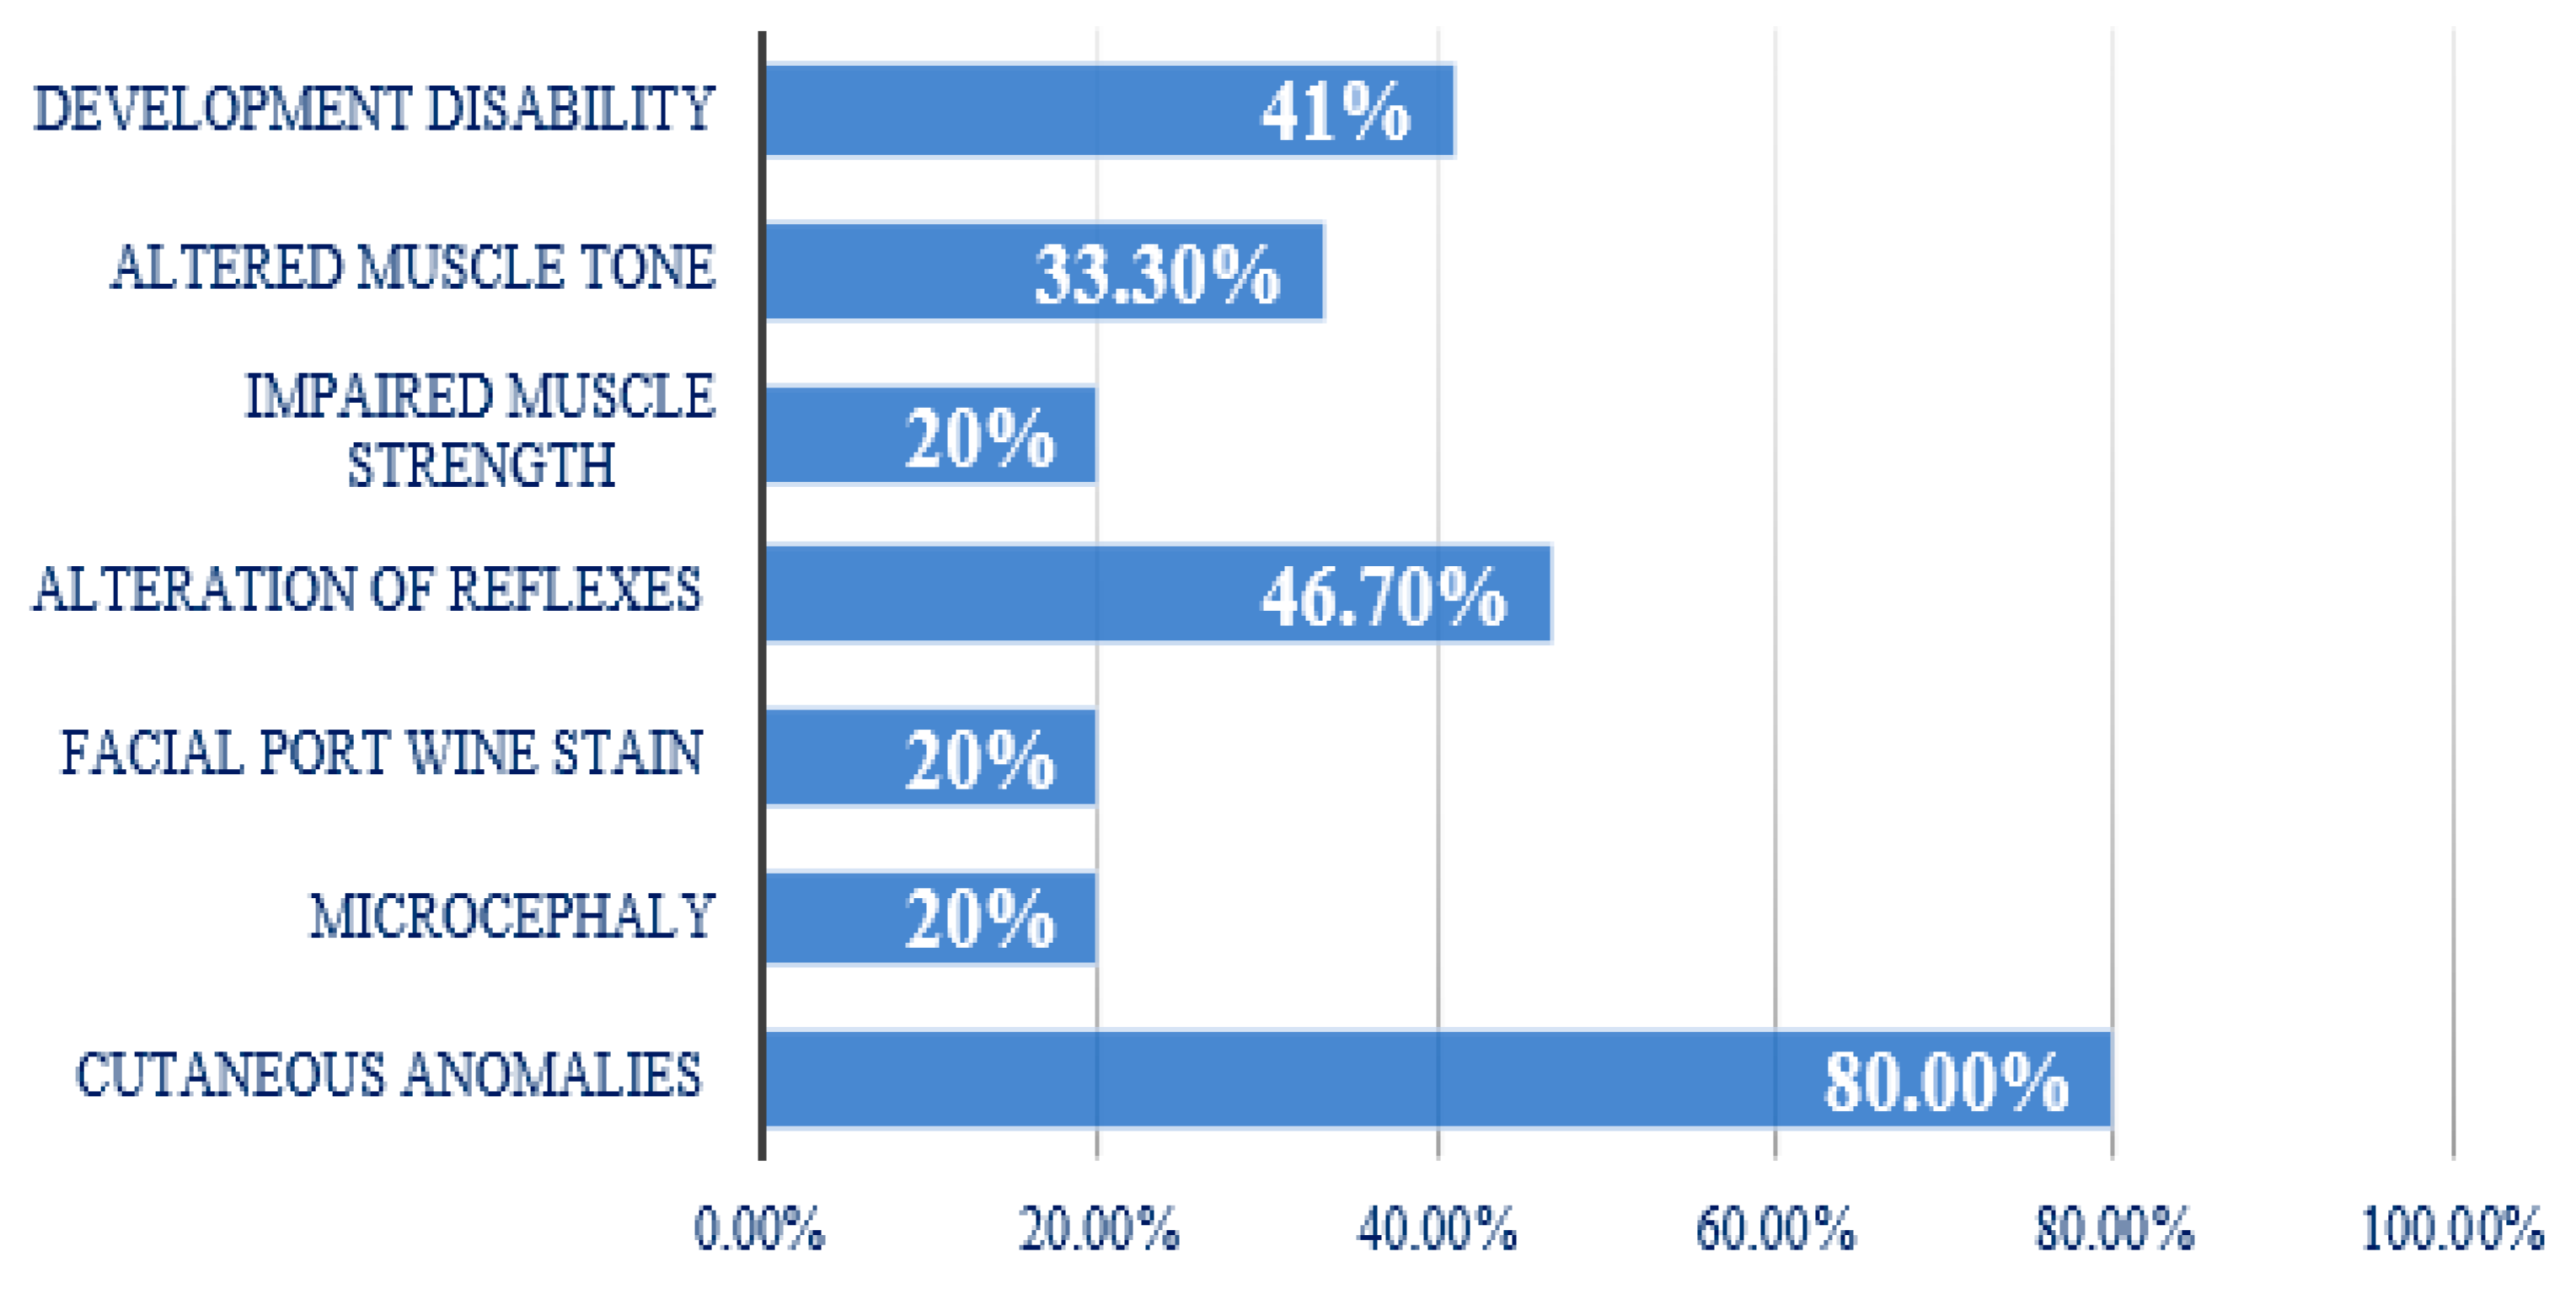

3.2. Clinical Aspects